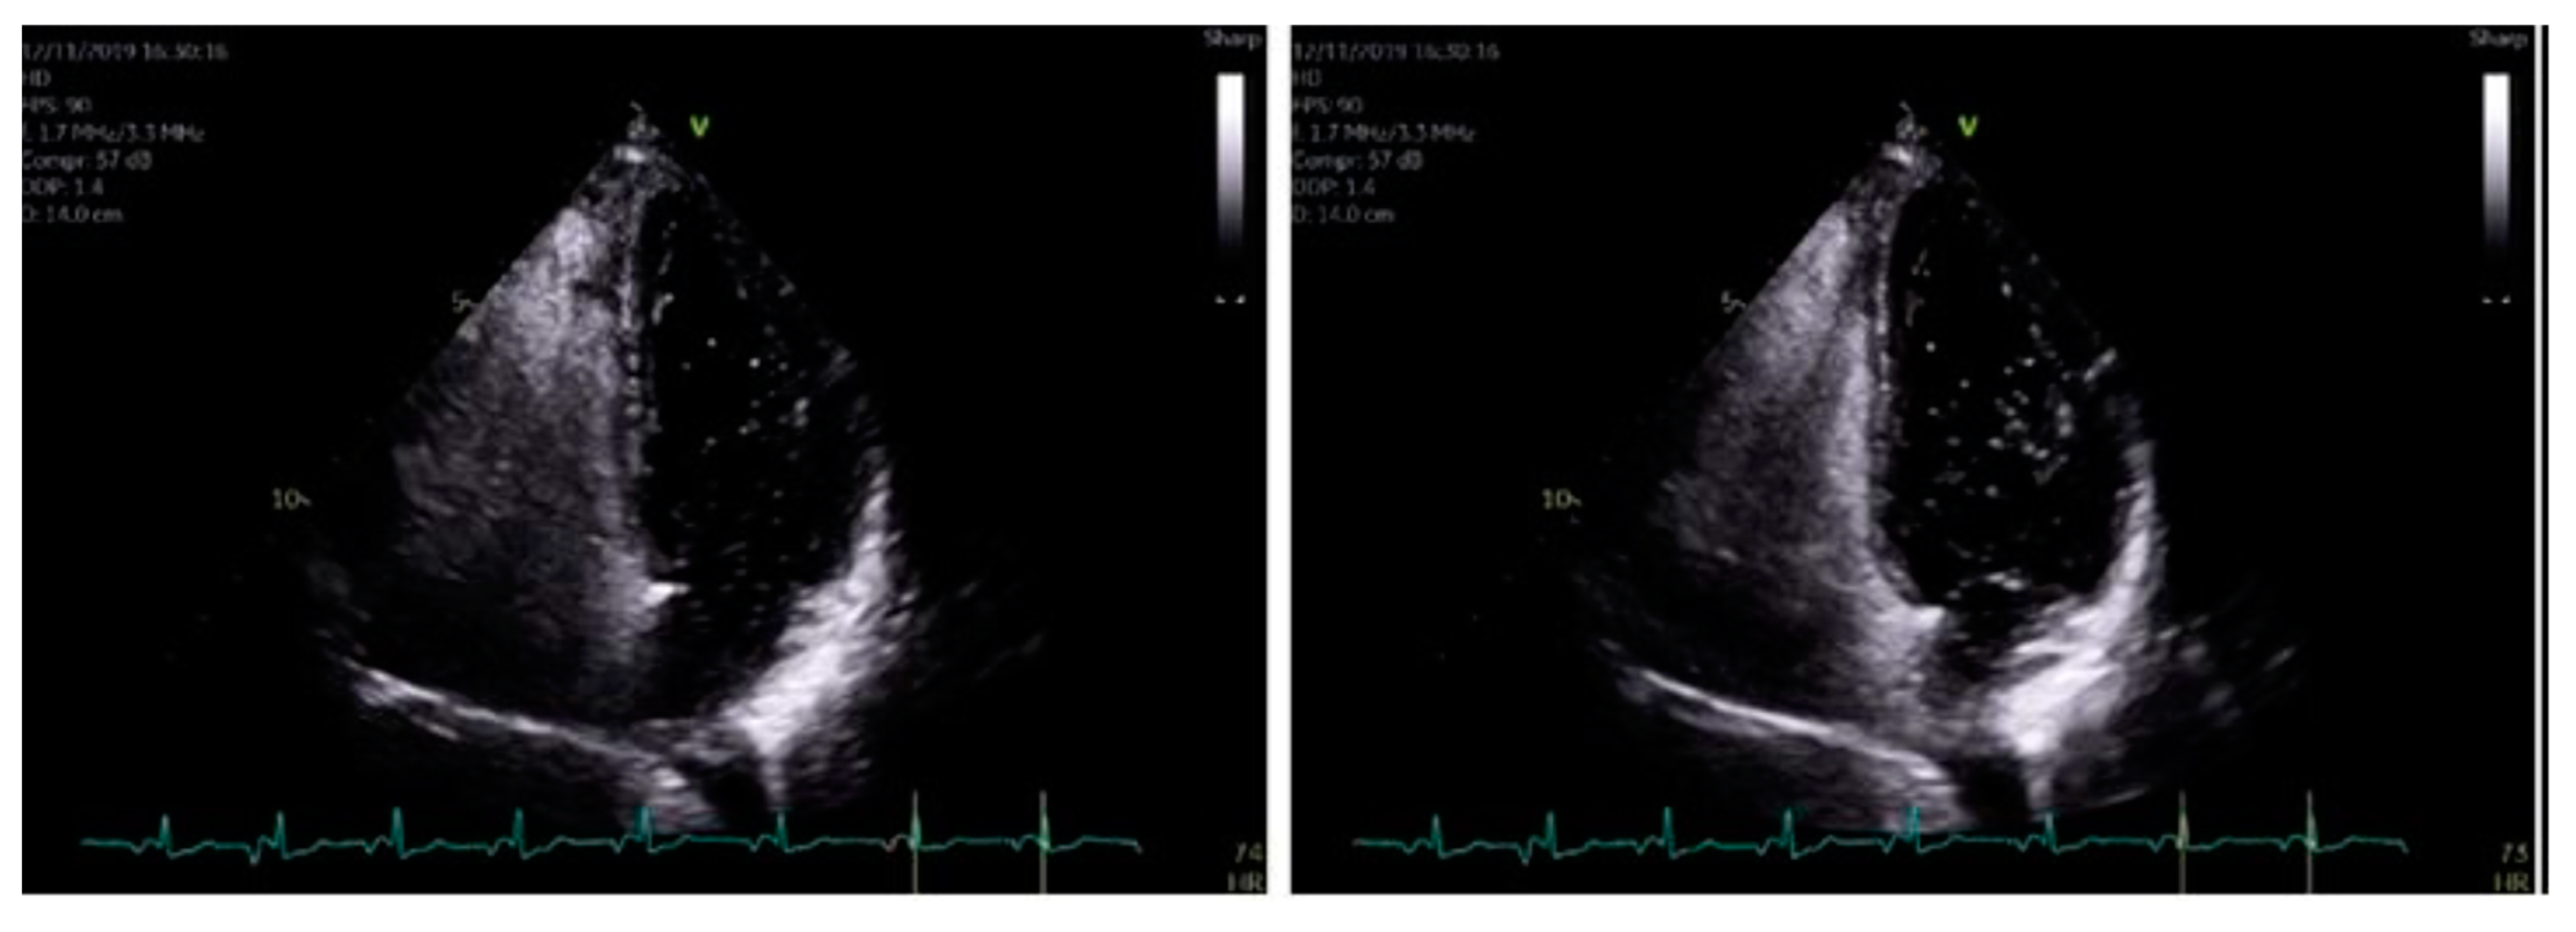

Figure 5.

When using bubble transthoracic echocardiogram, bubbles will be visualized entering the right heart using the apical four-chamber or subcostal views. Once there is complete opacification of the right atrium (RA), cardiac cycles are counted [5]. In patient without any type of shunt present, no bubbles should appear in the left heart. If, bubbles appear in the left atrium (LA) after three cardiac cycles, an intracardiac shunt is likely present.

The formal echocardiogram confirmed similar findings to that carried out by the bedside, with further results found. Hypokinesia of the mid to apical inferior segments was found along with a bright myocardium. Grade 1 diastolic dysfunction was also noted. Moreover, a bright pericardium was noted with no evidence of pericardial effusion. Also, there was no obvious flow across the interatrial septal wall. Despite that, her transthoracic echocardiographic images could not exclude the possibility of a PFO. Whilst her D-dimer levels came back as normal, her 24 h ECG tape confirmed five episodes of atrial fibrillation (min heart rate 90, max heart rate 146), with each episode separated by short intervals of sinus rhythm (atrial fibrillation lasted for 4 h and 43 min in total). Furthermore, her cardiac MRI confirmed preserved global left ventricle systolic function with hypokinesia at the apex (Figure 4A–C). A small apical infarction was noted with one non-viable segment (out of a total of seventeen for the entire left ventricle). As such, her admission of acute apical myocardial infarction (MI) was thought to be caused by an embolic phenomenon, precipitated by either paroxysmal atrial fibrillation (pAF) or a possible PFO. In order to delineate the cause, a bubble echocardiogram was carried out (Figure 5), something which is considered as a useful investigative tool for diagnosing cardiac wall malformations [5]. Subsequently, a reasonably sized PFO was found, wherein moderate amounts of bubbles were seen crossing the intra-atrial septum during normal breathing and during Valsalva maneuver (Figure 5). She was therefore discharged on aspirin 75 mg once daily, bisoprolol 1.25 mg twice daily, edoxaban 30 mg once daily (later doubled to 60 mg once daily) lansoprazole 30 mg once daily, and ramipril 1.25 mg once nightly. She was also due for outpatient work-up for PFO closure at a tertiary Centre.